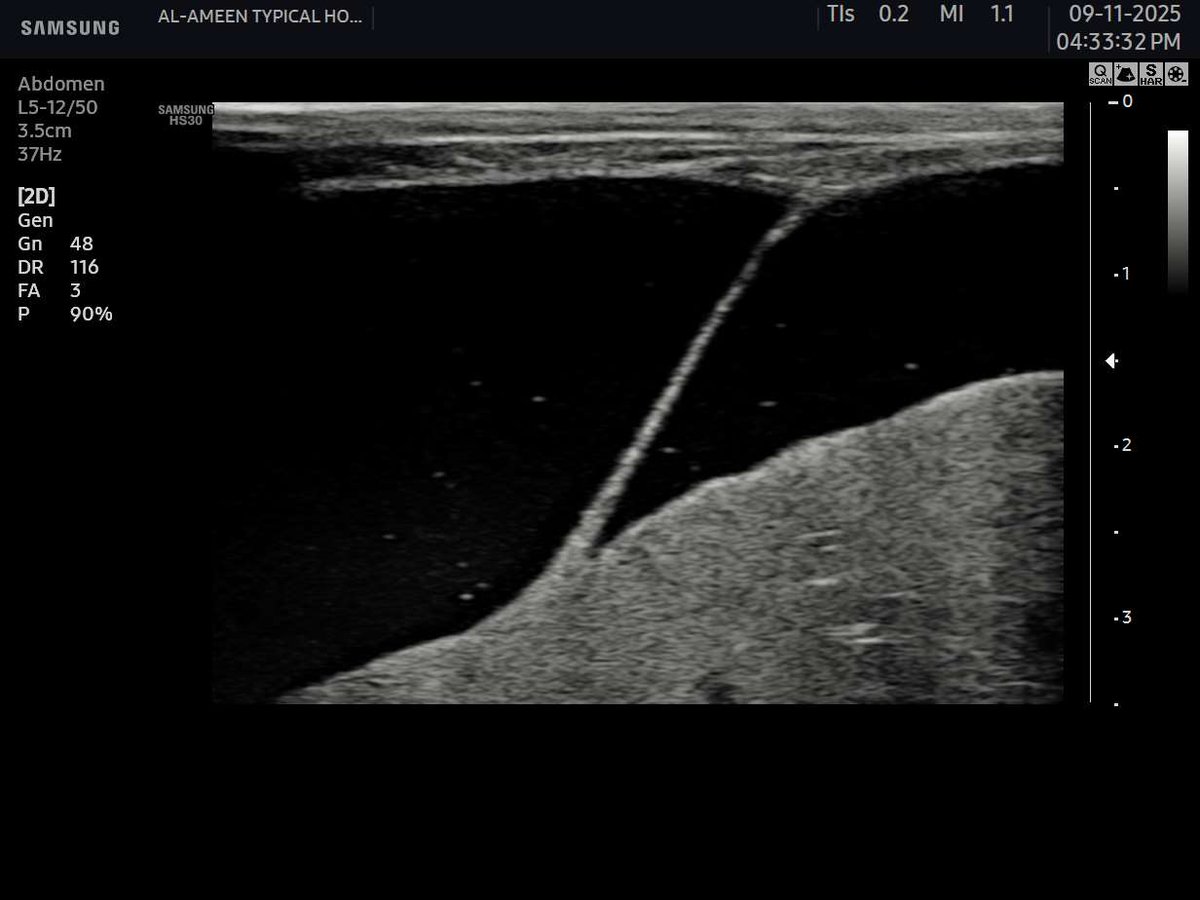

a 58 years male came with a diabetic foot And diffuse foot swelling Duplex U/S requested and done Your opinion? #EchoTech

a 58 years male came with a diabetic foot And diffuse foot swelling Duplex U/S requested and done Your opinion? #EchoTech

a 58 years male came with a diabetic foot And diffuse foot swelling Duplex U/S requested and done Your opinion? #EchoTech

a 58 years male came with a diabetic foot And diffuse foot swelling Duplex U/S requested and done Your opinion? #EchoTech

An emergent case of Popliteal artery occlusion Necrotizing fascitis (necrotizing soft tissue infection) Need urgent revascularization and debridement. #EchoTech